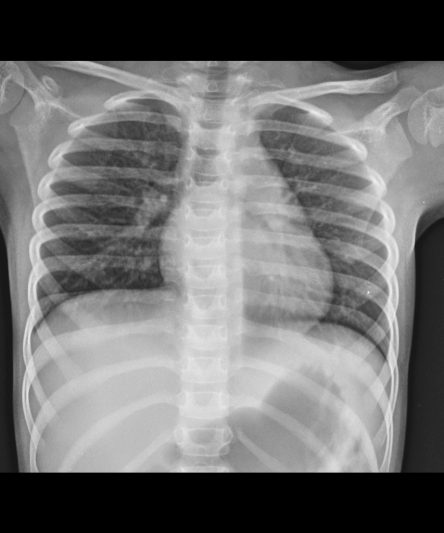

Microskan with Ultra high frequency can take the Lateral Lumbar Spine image of a 90 kg Patient with the correct image receptor